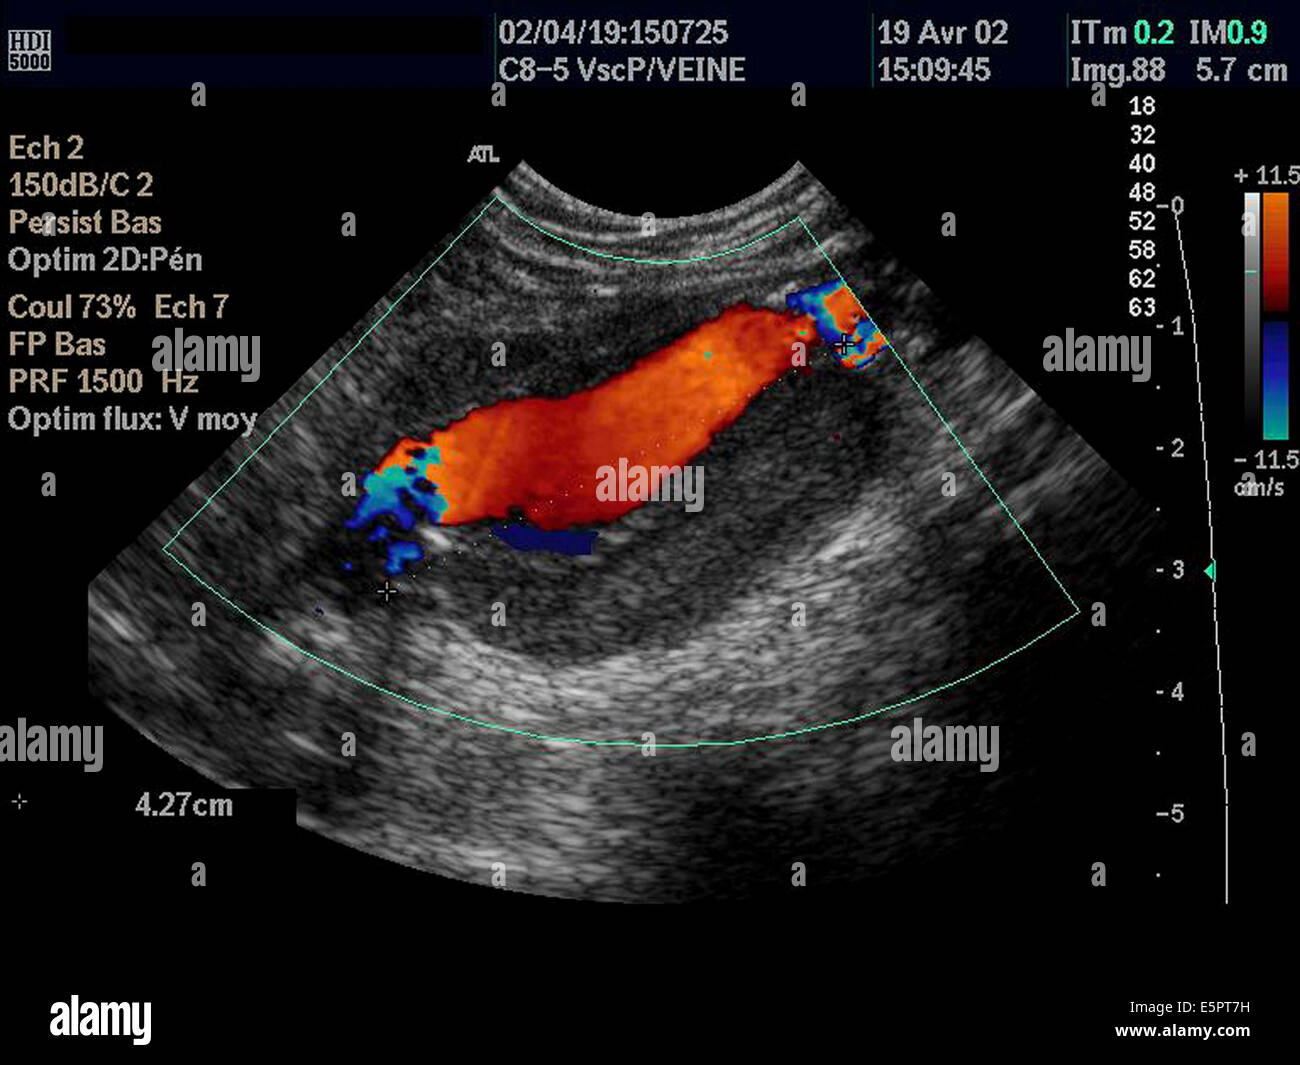

Un aneurisma aórtico abdominal es un agrandamiento de la parte baja de la aorta que se extiende a.

aneurisma de la aorta abdominal La aorta va desde el corazón hasta el. Recibe sangre con gran contenido en oxígeno. Cirugía vascularrupturas de aneurisma de la aorta abdominal: La cirugía de reparación abierta de aneurisma aórtico abdominal (aaa) se realiza para arreglar una parte dilatada de la aorta. Si tienes un aneurisma de la aorta abdominal en expansión, podrías notar lo siguiente: La incidencia de aaai en. En este artículo examen físico pruebas de detección y de diagnóstico ¿quiénes deben someterse a un examen de detección de aneurisma de aorta torácica? Los aneurismas aórticos aneurismas aórticos la aorta, que mide alrededor de 2,5 cm de calibre o diámetro, es la arteria más grande del cuerpo.

ABDOMINAL AORTIC ANEURYSMS Medical Yukti

Source: medicalyukti.blogspot.com